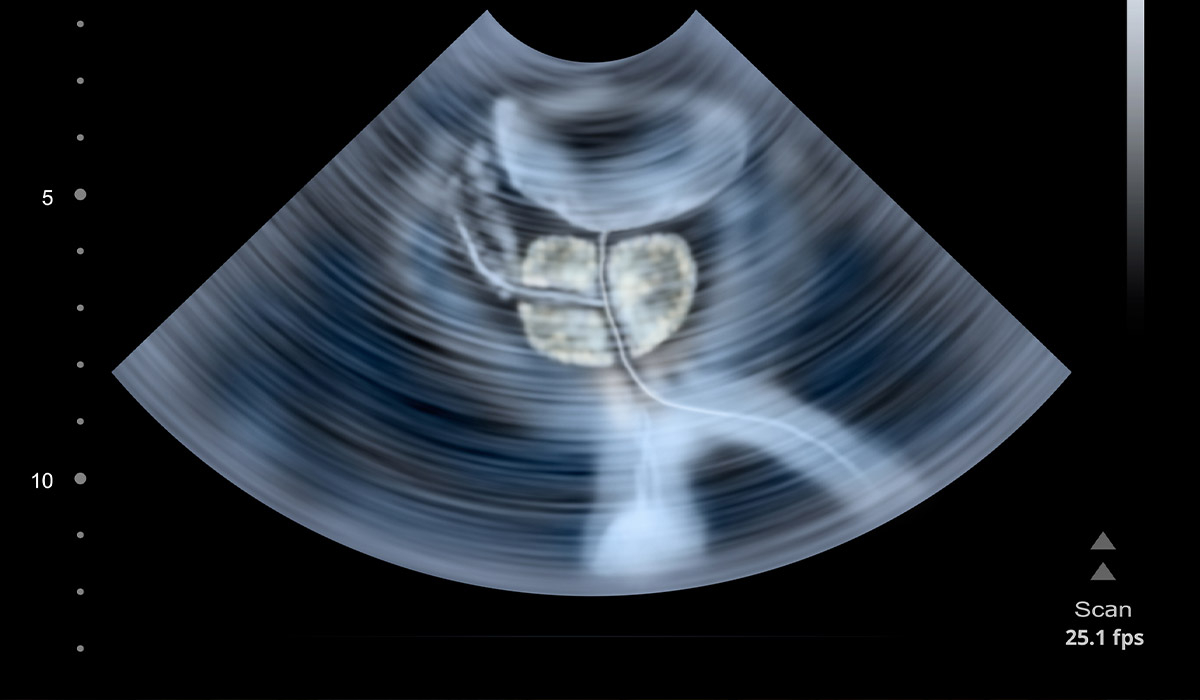

Особливість трансректального ультразвукового дослідження передміхурової залози полягає в тому, що діагностика виконується за допомогою введення тонкого сканера в пряму кишку пацієнта. Цей спосіб є максимально інформативним через особливості чоловічої анатомії. ТРУЗІ простати дозволяє спеціалісту так чітко візуалізувати контури і внутрішню структуру органу, що правильний діагноз поставити можна відразу після закінчення процедури. Крім того, прямо під час процедури ТРУЗІ можна взяти необхідну кількість тканини на біопсію і повторно не вдаватися до маніпуляції.

Найчастіше лікарі рекомендують пацієнтам один з двох видів УЗД передміхурової залози - трансабдомінальне (зовнішнє) або трансректальне (внутрішнє). Вибір методики залежить від віку пацієнта та мети дослідження. Чоловікам після 40 років рекомендовано проходити трансректальне УЗД.